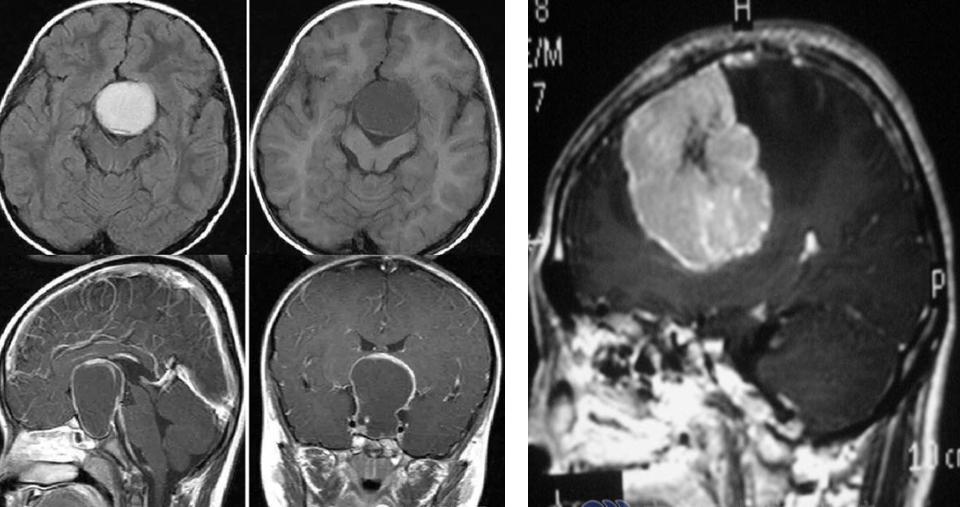

大家可以看到这张片子,大大的白颜色的就是脑内长瘤子了,脑里长的瘤子挤压了正常的空间,就像我的床只能睡一个人,我非要睡三个人,有一个人一定会挤到地下去的,那么脑内的空间也是这样,没有它的位置。

还有颅内出血,这种出血在儿科确实常见,尤其是小不点的孩子,家长容易忽视,比如摔了一个跟头,有的时候是慢性渗血,它不是急性出血,挫伤了以后慢性渗血,然后会导致孩子的呕吐,因为它一侧出血会导致孩子眼睛斜位、也会出现头疼、精神态势不好,这个也是在临床中一定要关注的。

还有我们老百姓知道的脑积水,脑积水它是因为脑内有一些保护我们脑组织输送营养、润滑细胞之间的液体,我们叫脑脊液。那么脑脊液它两种,一个是它排不出去了,就像家里的下水管子堵了,一定会把水池子堵上;还有一种水池子下水每分钟只能下10毫升,但是我们开巨大的管子,1分钟可以1万毫升,那就相当于分泌多了,它就会造成脑积水,脑脊液多了,出不去或是分泌多了,小不点的孩子就会出现大脑袋,所以我用了一个脑积水的一级、二级、三级来表示:

大家可以看到灰蓝色的越大,脑积水越厉害,所以孩子也会表现为呕吐。如何发现脑积水的这个情况是被占位、被颅压高导致非常容易,做一个影像学的片子,比如做一个CT、做一个磁共振,就可以看到脑子里长没长瘤子、有没有出血、有没有压力高造成脑积水,这个问题就非常容易地解决了。